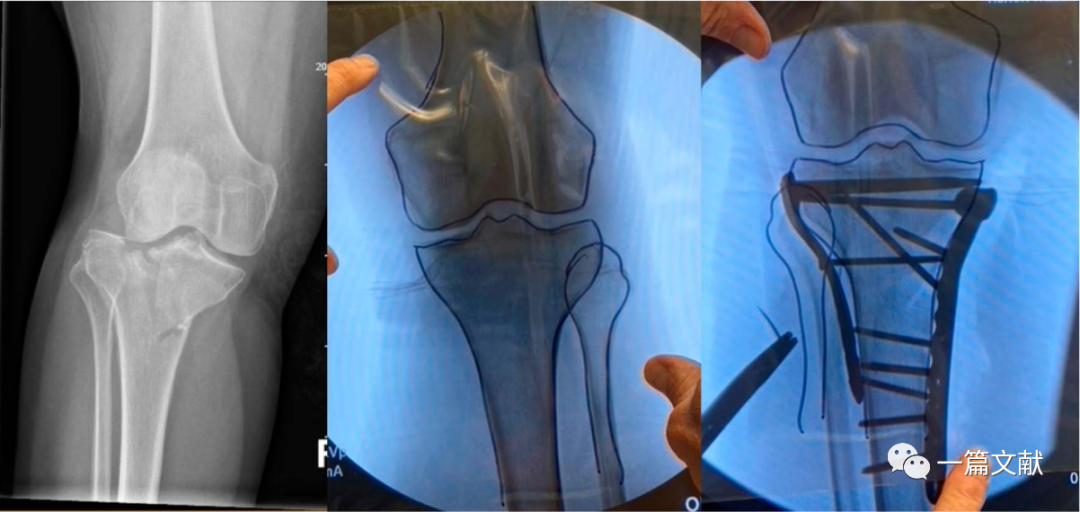

在患者入手术室后,行无菌铺单前对健侧肢体C臂机透视,并将图像保存于右侧显示屏。若术中需要在垫高状态下进行,则此时应该将健侧肢体垫高透视,尽量做到与术侧肢体一致。当获得满意的正侧位图像后,用薄的描写纸或透明胶片覆盖显示屏图像,并用记号笔对健侧骨骼形态进行临摹。此时我们就获得了患者健侧骨骼轮廓,将其翻转,以此作为标准,对于术中指导和术后检验复位均起重要作用。具体如下图:

上图左侧为健侧标准前后位X片,右侧为临摹的骨骼轮廓。

上图左侧为患侧肢体,中间为临摹的健侧骨骼轮廓。右侧图将临摹后的纸张翻转后贴于C臂机显示屏,作为术中复位模板。术后亦可利用该模板对固定后的骨折进行比对。